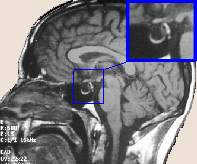

La Silla Turca forma un hueco situado en la vertiente endocraneal del hueso esfenoides.

Su nombre no es casual, pues tiene una curvatura asemejándose al asiento de una silla, con la forma exacta para cobijar y servir de alojamiento a un órgano clave en la regulación de las hormonas: la hipófisis.

adelgazamiento de glandula hipofisaria con ocupacion de silla turca por liquido cefalo raquideo. Silla turca vacia

adelgazamiento de glandula hipofisaria con ocupacion de silla turca por liquido cefalo raquideo. Silla turca vacia. Que significa esto en un informe de resonancia magnerica